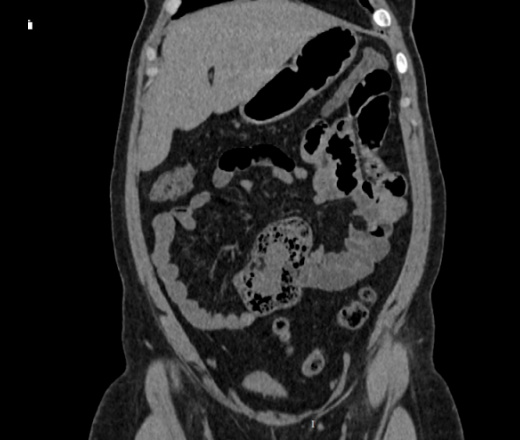

Здравствуйте, женщина 40лет, жалобы на увеличение живота, началось с 2023 года, жалобы на запоры временами и на водянистый стул, подскажите что здесь в области баугиниевой заслонки? инвагинация слепой кишки в подвздошную? что рекомендовать?

В классической рентгенологии такое смещение слепой кишки называли - мобильная слепая кишка.

Описал бы как "кт-признаки болезни Крона (терминальный илеит)", порекомендовал бы колоноскопию с биопсией